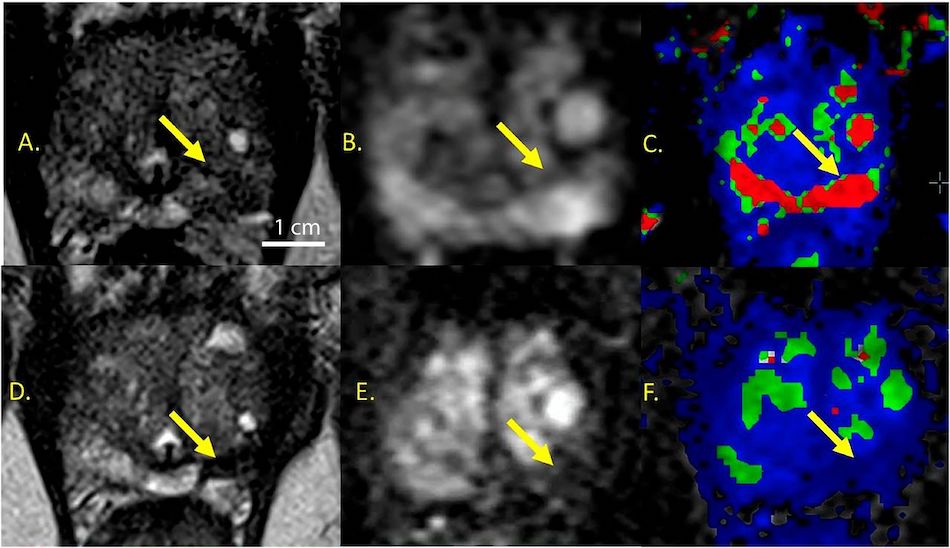

Gold nanoparticles allowed precise thermal ablation of prostate tumors. Credit: Nanospectra Biosciences.